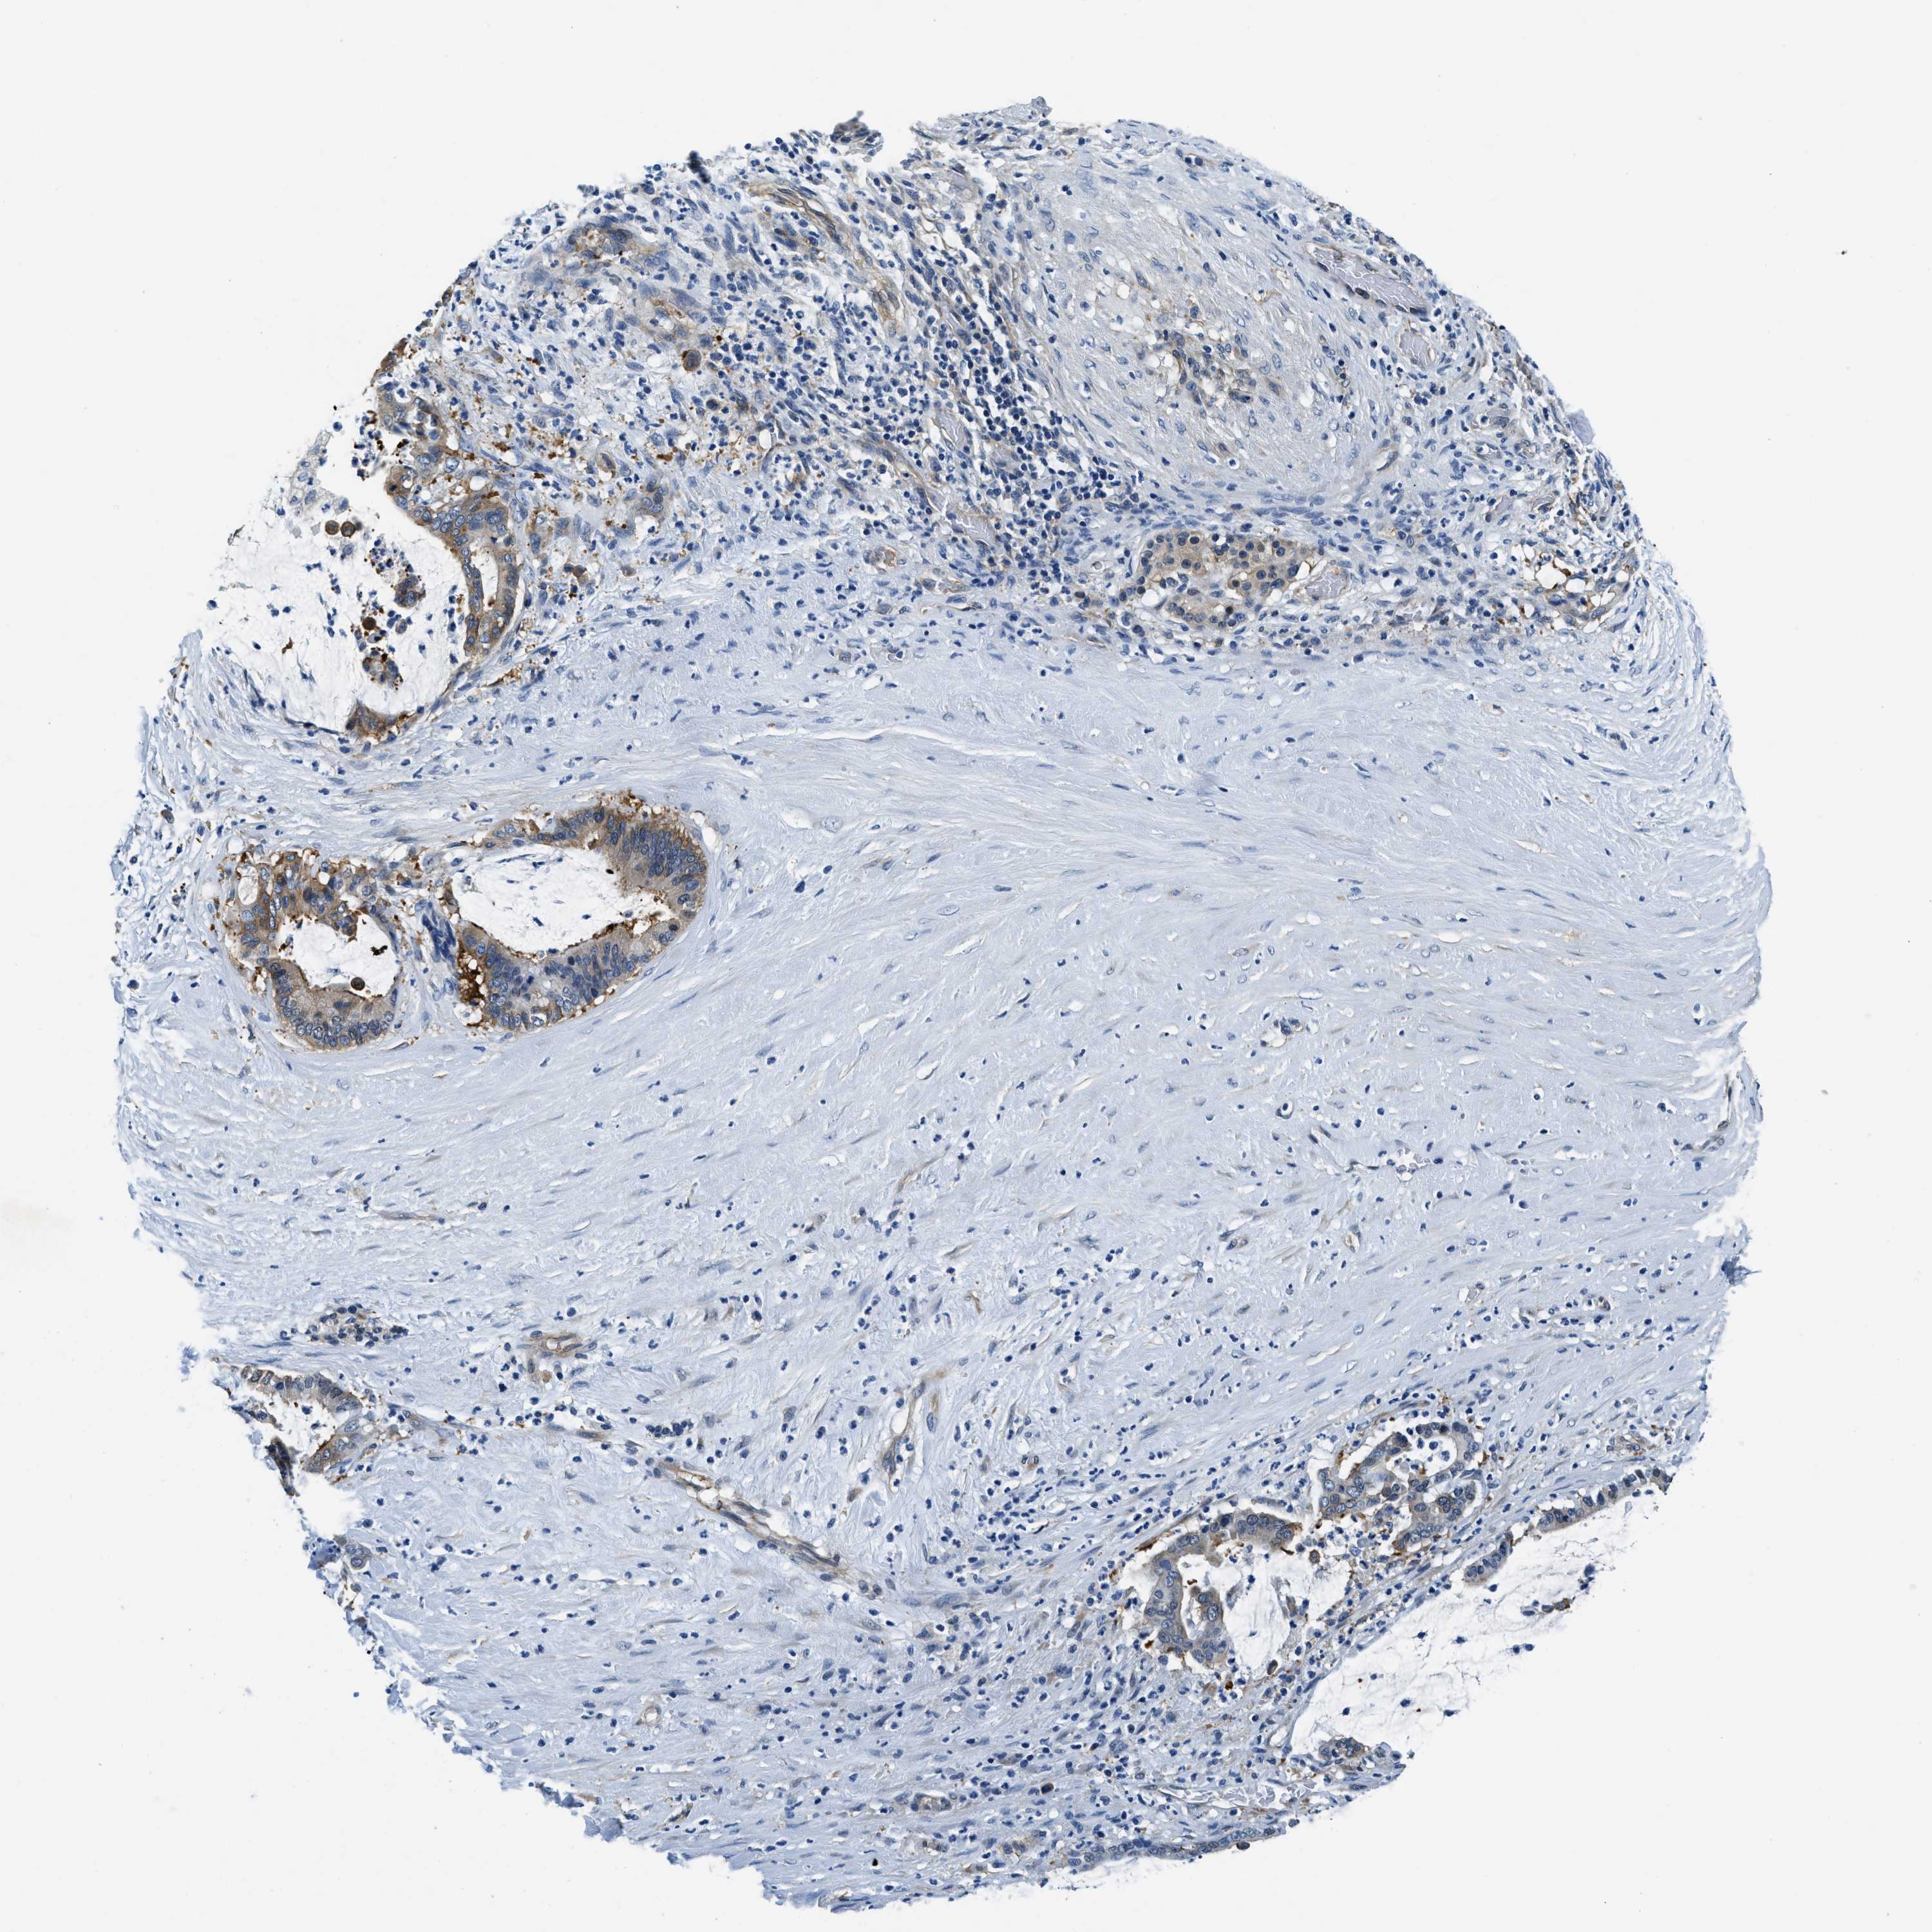

PANCREATIC CANCER - Protein expressioni

A mouse-over function shows sample information and annotation data. Click on an image to view it in a full screen mode. Samples can be filtered based on level of antibody staining by selecting one or several of the following categories: high, medium, low and not detected. The assay and annotation is described here.

Note that samples used for immunohistochemistry by the Human Protein Atlas do not correspond to samples in the TCGA dataset.

Antibody stainingi

Antibody staining in the annotated cell types in the current human tissue is reported as not detected, low, medium, or high, based on conventional immunohistochemistry profiling in selected tissues. This score is based on the combination of the staining intensity and fraction of stained cells.

Each image is clickable and will lead to virtual microscopy that enables deeper exploration of all samples and also displays staining intensity scores, fraction scores and subcellular localization as well as patient and tissue information for each sample.

Antibody HPA018116

Staining

High

Medium

Low

Not detected

Intensity

Strong

Moderate

Weak

Negative

Quantity

>75%

75%-25%

<25%

None

Location

Nuclear

Cytoplasmic/membranous

Cytoplasmic/membranous,nuclear

Adenocarcinoma, NOS